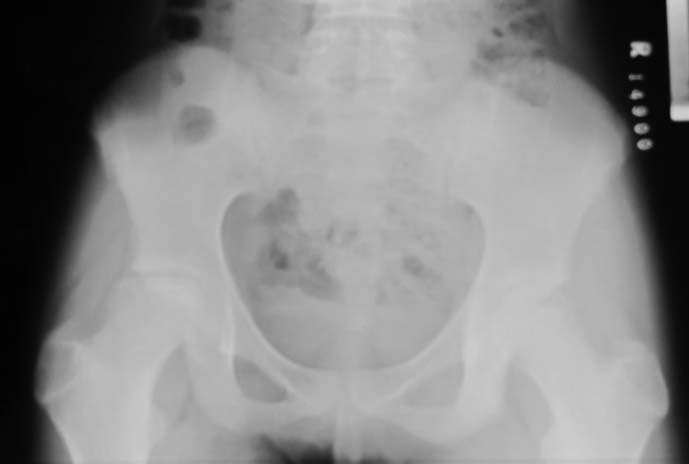

Обратилась пациентка 12 лет, 7 месецев назад стали замечать хромоту.

Лечилась консервативно. Снимки в приложении. Выражена хромота, резко ограничены отведение и ротационные движения бедра. Чем можно помочь сейчас или "поезд ушел"? Прогноз? Буду блогодарен любым соображениям.

Аршак! Сделай КТ, лучше трехмерку. Дальше будем решать. Процесс по восстановлению эпифиза завершился, но с явной деформацией. АИФ

У меня более взрослые больные с последствиями и поэтому вопрос к педиатрам-специалистам по заболеванию Пертес. Не вызывает ли сомнения диагноз? Меня смущает небольшой срок истории и возраст пациентки. Болезнь может встречаться до 12 летнего возраста, но к этому времени у многих заканчиваются все стадии развития заболевания, включая вовлечение в процесс ацетабулума. Обычно процесс течение заболевания немного дольше, чем "7 месецев назад стали замечать хромоту".

Встречается ли заболевание без характерного склероза с молниеносным течением в 12 летнем возрасте? По-моему, изчезновение головки в короткий срок характерно для септических состояний, и поэтому на первое место в дифференциальной диагностике я бы поставил на септический артрит? Заново собрать анамнез на восспалительный процесс, анализы, пункция?

Доисследование покажет, что от чего, но это не сохранит головку бедра. Лечение состоит в ограничении нагрузки с периориентацией головки. От подвывиха головки сохранит варусная остеотомия, и в дальнейшем создаст опору. После операции движение в суставе на Continuous passive motion.

In this age prognosis is bad , but I think that she will improve after Vagus osteotomy -the goal is to remove necrotic part of the head from the weight bearing edge of the acetabulum